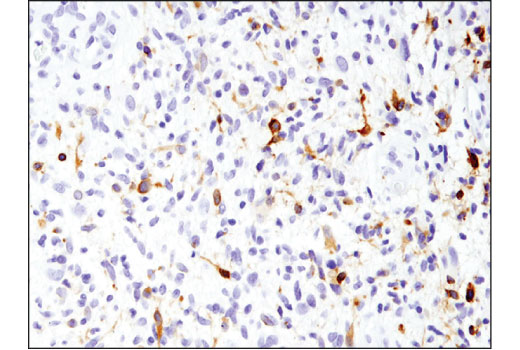

EGF Receptor vIII (D6T2Q) XP Rabbit mAb

64952S

100ul